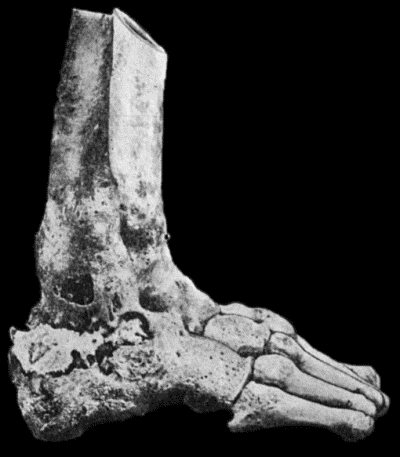

| 118. | Shaft of the Femur after Acute Osteomyelitis | 444 |

| 119. | Femur and Tibia showing results of Acute Osteomyelitis | 445 |